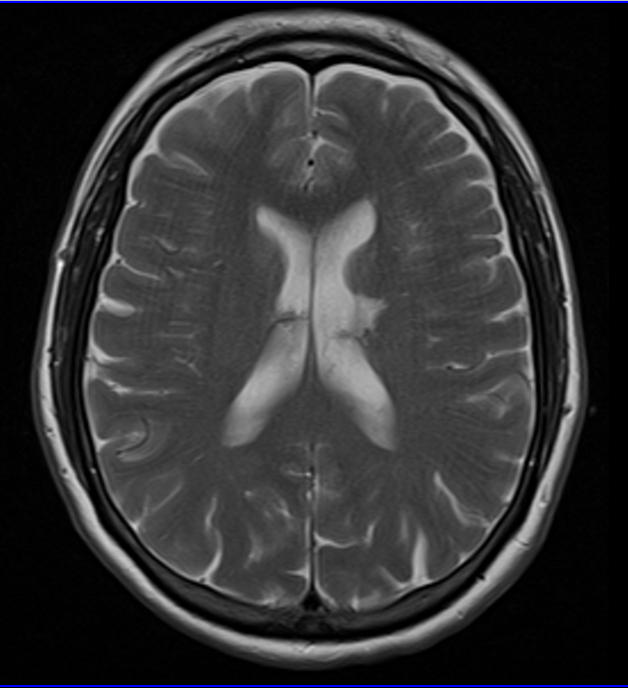

Stroke is a common disease seen by emergency physicians with over 800,000 new cases in the U.S. each year (Mozaffarian, 2016). Both ischemic (embolic or thrombotic) and hemorrhagic stroke patients frequently have derangement of their blood pressure, in addition to the fact that 70% of stroke patients have hypertension as a chronic condition (Miller, 2014). Acute hypertension management has long been a vital component of the medical management of stroke patients. However, guidelines are frequently changing and recent literature has demonstrated that large fluctuations in systolic pressure, whether up or down, lead to adverse outcomes (Anderson, 2013). In this brief review, I want to lay out a framework for dealing with hypertension in stroke patients, based on recent literature and guidelines from the American Stroke Association (ASA).